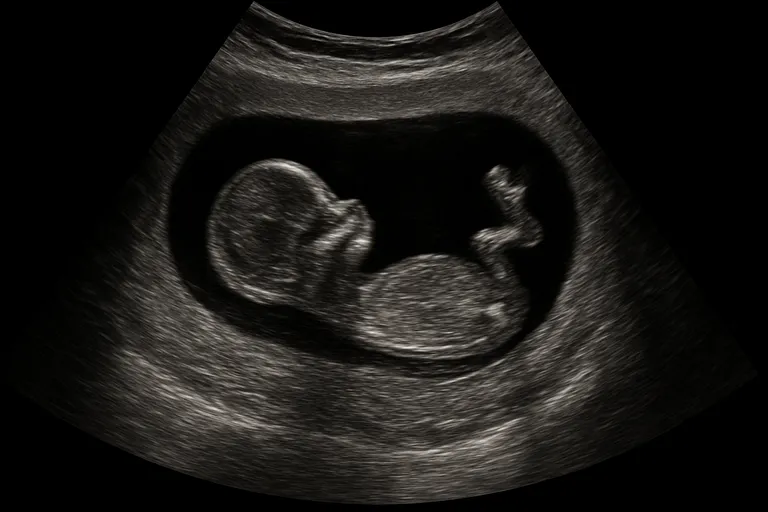

Bij een echo met 10 weken zie je meestal een duidelijk gevormd kleintje met een herkenbare hoofd-romp, armpjes en beentjes, en vaak al handjes en voetjes. Het hartje klopt ritmisch en je ziet regelmatig dat je baby korte, schokkerige bewegingen maakt; bij een 10 weken echo baby beweegt vaak al, ook al voel je dat zelf nog niet. De echoscopist meet de CRL (kruin-stuitlengte) om je termijn vast te stellen, beoordeelt de dooierzak, de aanleg van de placenta en de navelstreng, en kijkt of je zwanger bent van één baby of een tweeling.

Je krijgt meestal 2D-beelden te zien; dat is het scherpst voor datering en basiscontrole. Soms zijn kleine details, zoals het neusbotje of vingers, al vaag te onderscheiden, maar de uitgebreide orgaanscreening volgt later, bijvoorbeeld bij de 13-weken echo. Het geslacht is met 10 weken nog niet betrouwbaar te zien. De echo is vaak uitwendig via je buik; als de ligging of beeldkwaliteit tegenzit kan een inwendige echo helpen om alles helder in beeld te brengen.

Beeld van je baby: groei, beweging en hartslag (echo baby 10 weken, 10 weken echo baby beweegt)

Bij een echo rond 10 weken zie je dat je baby flink gegroeid is: de kruin-stuitlengte ligt gemiddeld rond 3 à 4 centimeter en het hoofd is nog relatief groot ten opzichte van het lijf. Armpjes en beentjes zijn duidelijk zichtbaar en je ziet vaak korte, schokkerige bewegingen zoals strekken, draaien of even ‘zwaaien’ met een handje, ook al voel je dat zelf nog niet.

Het hartje klopt snel en ritmisch, meestal rond 150-170 slagen per minuut, wat op deze termijn normaal is. Je ziet vaak ook de dooierzak en de beginnende placenta. Dit alles geeft een levendig beeld en helpt je echoscopist te beoordelen of de groei en vitaliteit passen bij 10 weken zwangerschap.